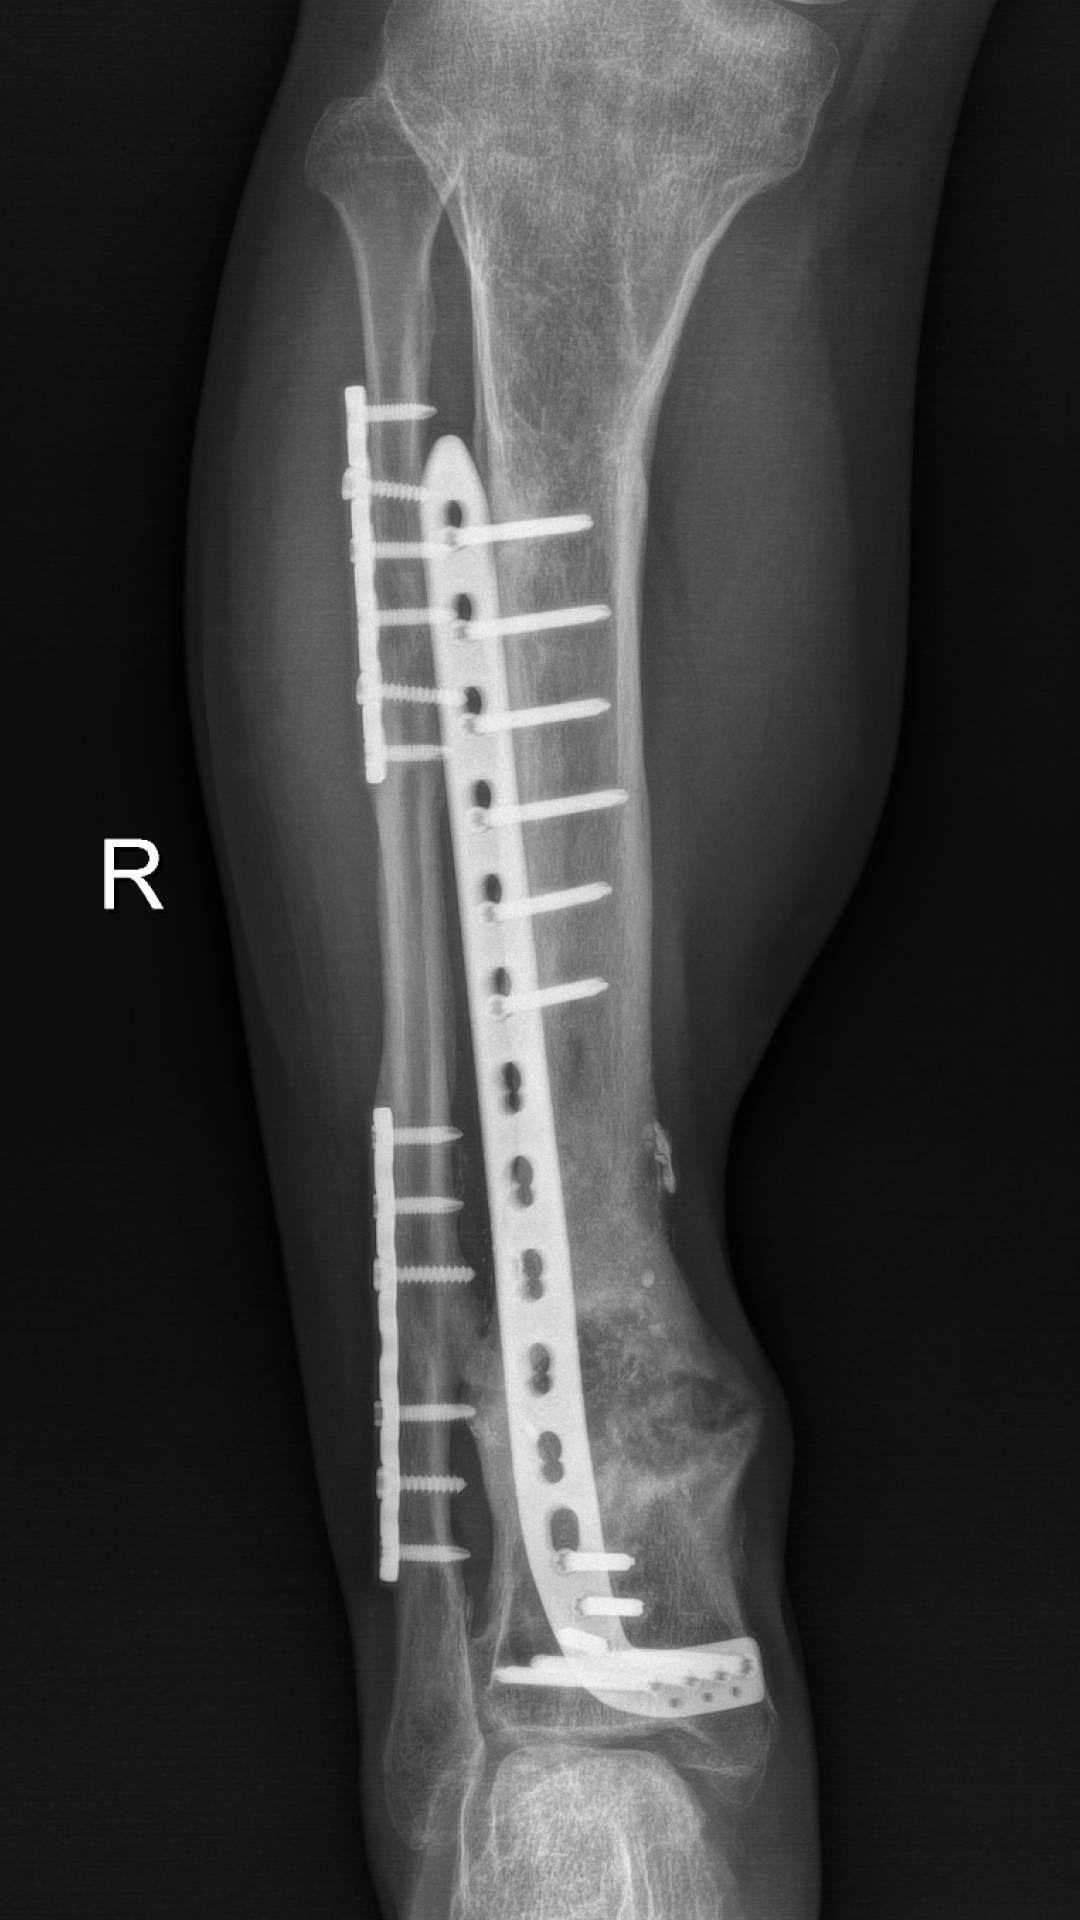

3、骨愈合

4、内固定去除

经过反复评估及推敲,徐杨主任医师决定分三步进行:首先分次清创,在保住残留血供及神经同时,彻底清创;利用长管状骨节段性缺损诱导膜再生技术(masquelet技术)修复骨缺损,最后通过肌腱转位替代、踝关节松解,恢复功能。这其中每一步都不容有失,困难重重,极具挑战。在医患通力配合下,多次按既定方案为小罗成功施行手术,小罗保住了右腿,经过近一年的正常行走生活,近日返院进行最后的钢板拆除手术。